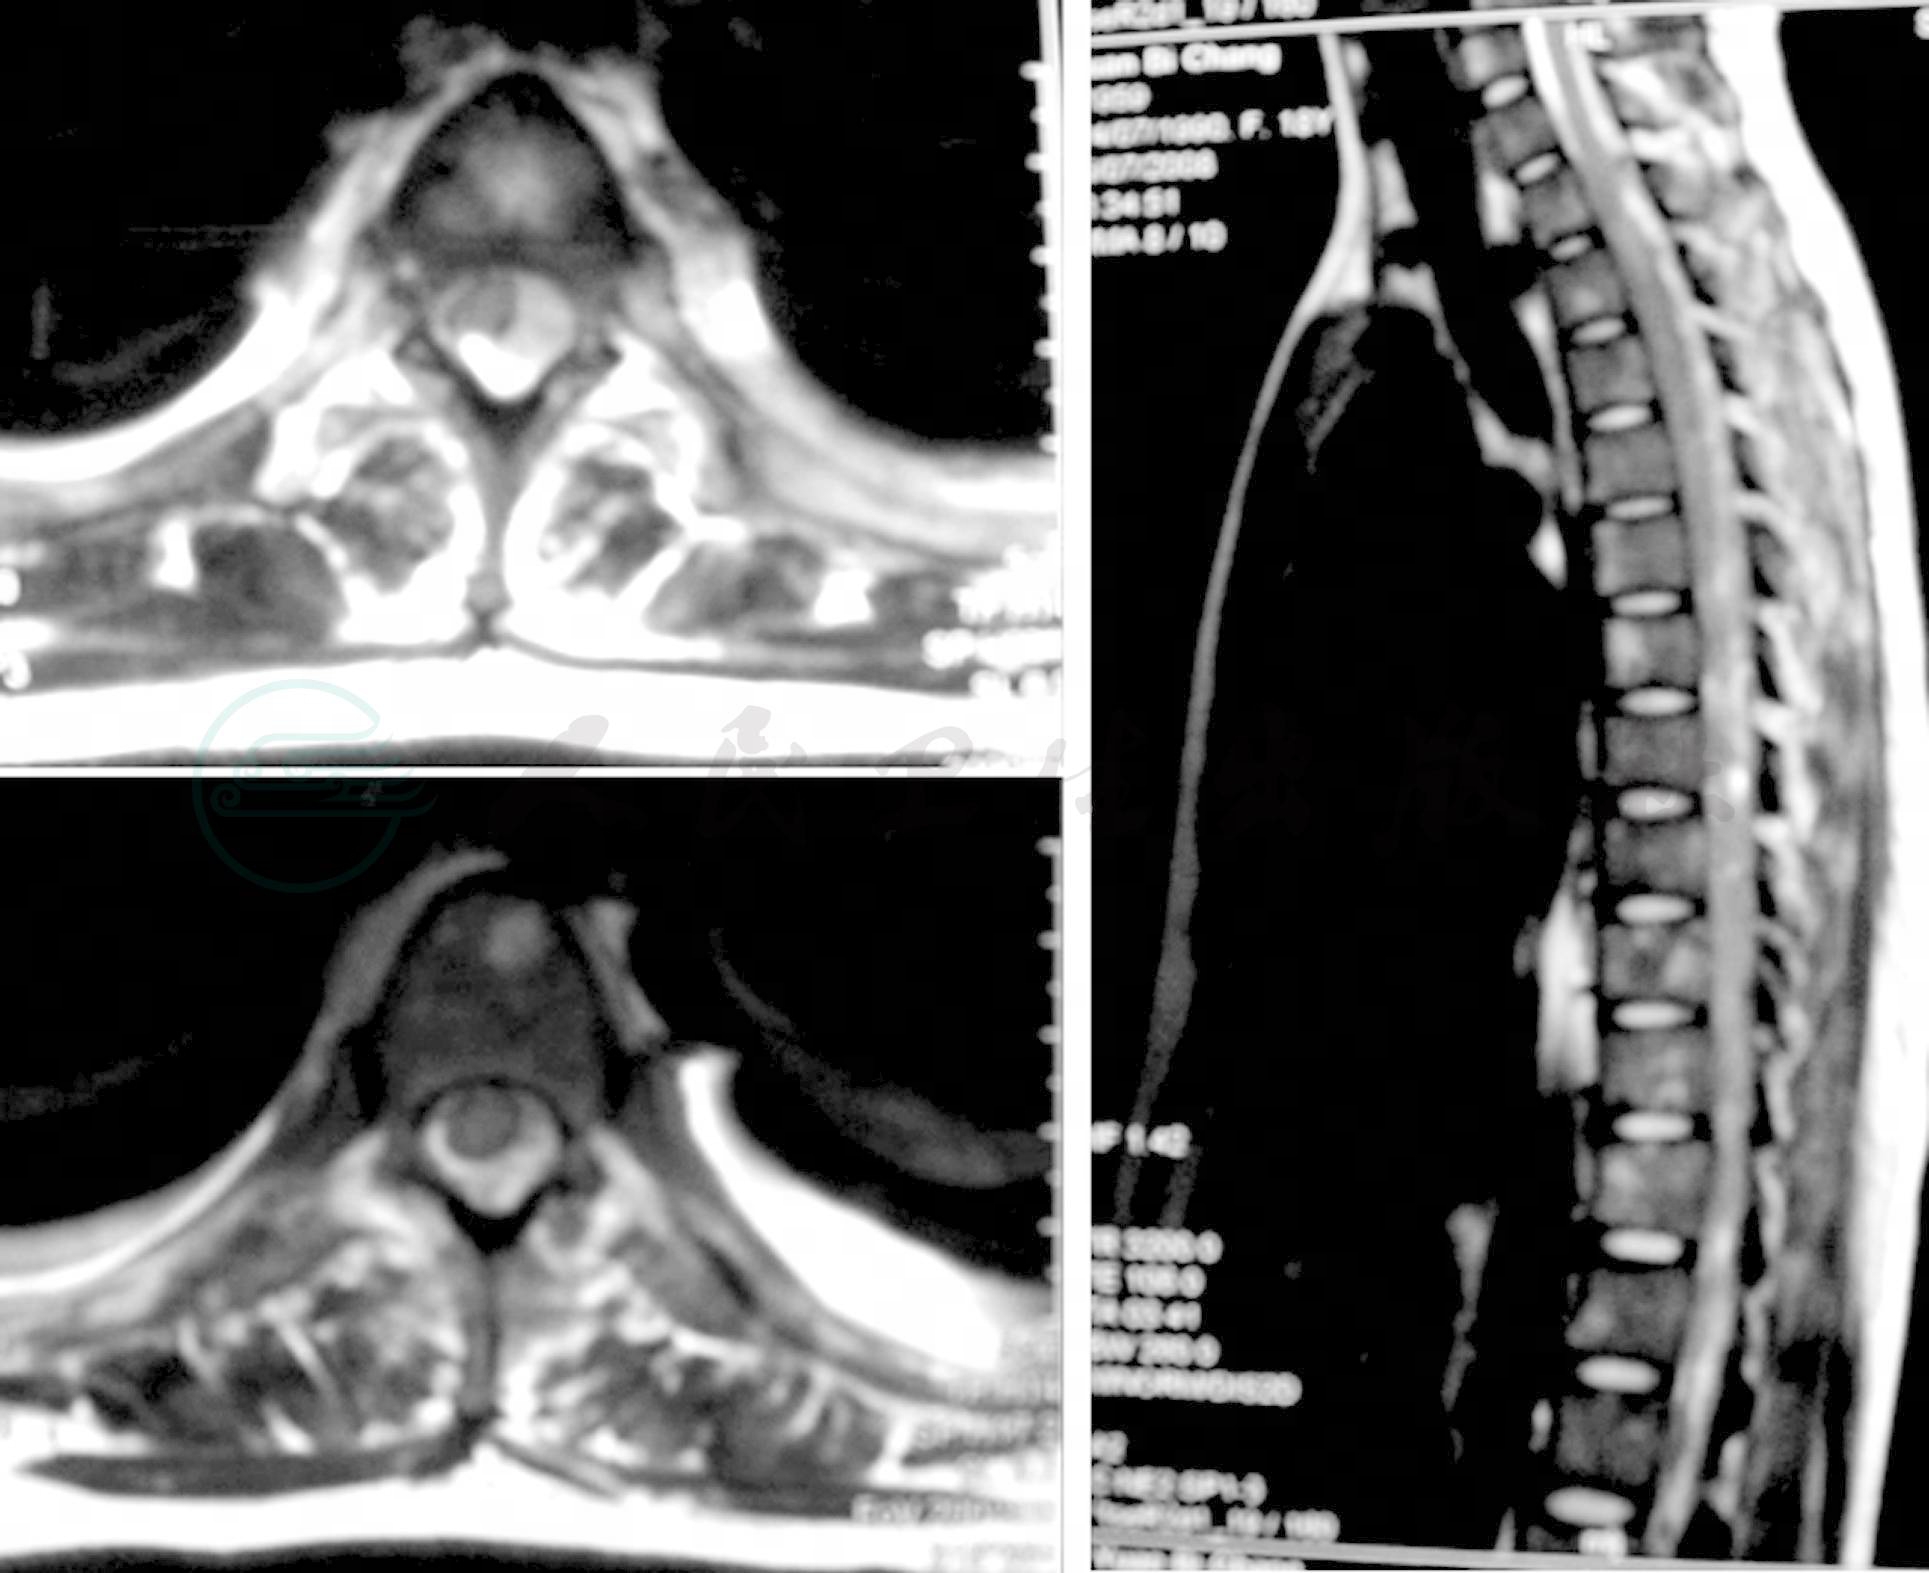

胸椎MR平扫及增强扫描

(2008-7-28)下段颈椎和胸椎多个椎体内见斑、点状异常信号,以稍长T1,长T2信号为主,部分呈短T1信号改变,椎体形态尚规则,椎间隙未见狭窄,椎间盘信号尚无改变;胸段脊髓信号不均匀,蛛网膜下腔内异常信号,脊髓周围被软组织肿块环形包绕,并沿着椎间孔生长,部分通过椎间孔突入椎旁间隙,脊髓受压明显,变形变细;椎体旁见梭形软组织肿块,与椎体分界清楚,增强扫描见椎体内、脊髓周围及椎旁软组织轻度不均一异常强化(图2)。

图2 胸椎MR平扫及增强扫描

下颈段及胸段脊柱多个椎体,脊髓周围软组织肿块包绕,双侧椎旁软组织肿块

双侧胸腔内见胸水,胸膜见多个小结节样影(图3)。

图3 胸部MR平扫及增强扫描

胸膜多发结节,双侧胸腔少量胸水

影像诊断:

(1)下颈段及胸段脊柱多个椎体,脊髓周围软组织肿块包绕,双侧椎旁软组织肿块,胸膜多发结节,考虑血液系统疾病(白血病或淋巴瘤)的可能性大。

(2)双侧胸腔少量胸水。